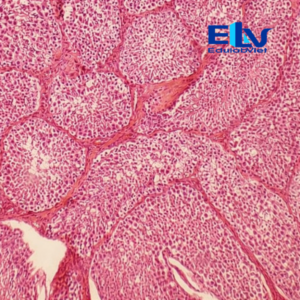

Tiêu bản tinh hoàn thỏ cắt ngang là mẫu tiêu bản hiển vi cố định thể hiện rõ cấu trúc vi thể của tinh hoàn, đặc biệt là các ống sinh tinh và các giai đoạn phát triển của tế bào sinh tinh. Sản phẩm phù hợp cho giảng dạy và thực hành môn Sinh học, Giải phẫu học, Mô học động vật.

Cấu trúc mô rõ ràng:

Quan sát rõ các ống sinh tinh, tế bào sinh tinh ở nhiều giai đoạn phát triển và mô kẽ tinh hoàn. -

Màu nhuộm đẹp – độ tương phản cao:

Tế bào được nhuộm đậm, sắc nét, giúp dễ dàng quan sát dưới kính hiển vi quang học. -